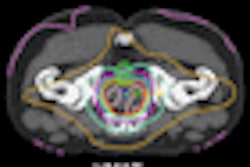

The researchers fused the follow-up CT scans with the planning scans of each patient to maximize rib alignment from the fracture site to the costovertebral joint. After the entire fractured rib and the site of the fracture were contoured, equivalent uniform dose and doses with and without tissue inhomogeneity correction were calculated.